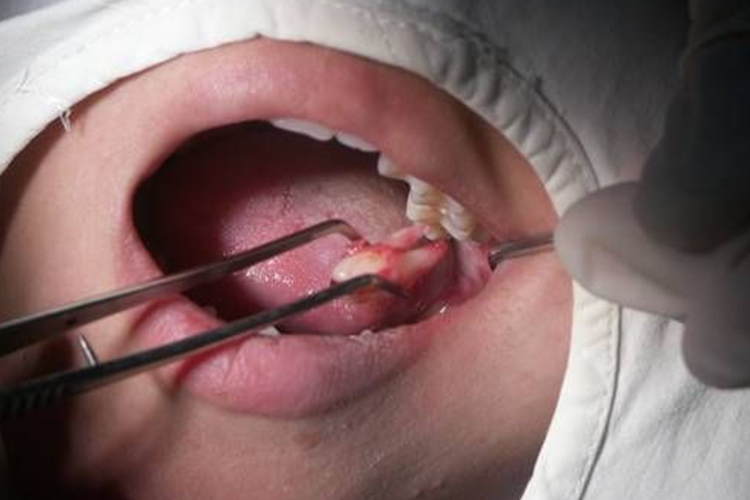

拔除智齿

当邻牙阻力及骨阻力解除后,即可使用牙挺及牙钳顺利拔除患牙。但对于分牙后拔除的牙,应将拔除的牙体组织拼对检查是否完整,如有较大缺损,应仔细检查牙槽窝并将遗留残片取出。